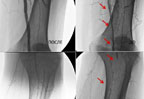

Arterial rekonstruksiyaların nəticələri